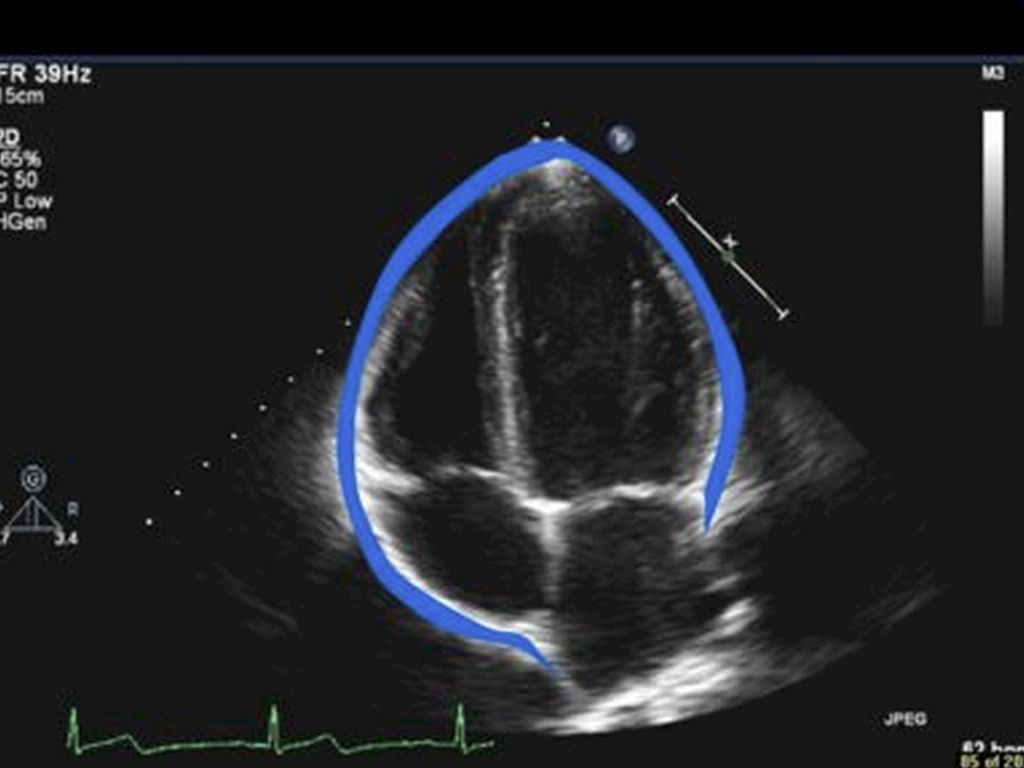

Pericardial Effusion is an abnormal amount of fluid between the heart and the pericardium, which is the sac surrounding the heart. Pericardial effusions are associated with many different medical conditions. Most pericardial effusions are not harmful, but large pericardial effusions can cause problems by impairing heart functions.

Most pericardial effusions are caused by inflammation of the pericardium, a condition called pericarditis. As the pericardium becomes inflamed, extra fluid is produced, leading to a pericardial effusion.